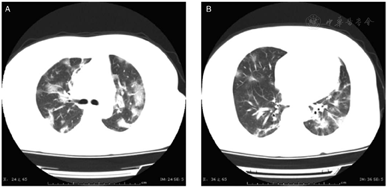

A definitive diagnosis of 2019-nCoV was acquired by realtime fluorescence-based RT-PCR. As shown in Table 3, about 80% of the patients had normal or decreased white blood cell counts, and 72.3% (99/137) of the patients developed lymphocytopenia, consistent with the main characteristic of viral infection. The lung images of most patients showed abnormal characteristics that involved both of the lungs in most cases (116/137, 84.7%). Figure 2 shows representative lung images of a patient in which lesions developed in multiple lobes, most of which were dense, and ground-glass opacity co-existing with consolidation or cord-like shadows.

Nevertheless, these atypical initial symptoms deserve similar attention with the more common symptoms. For example, there have been reports of patients with NCP presenting with diarrhea as the initial symptom of disease onset.[14] Some patients presented with elevated troponin levels and myocarditis.[15] Others developed headache, myalgia, and other symptoms similar to those of influenza.[14] It should be emphasized that the authors observed that some patients in the outpatient clinic even had no obvious symptoms, or came to see the doctor only with "discomfort." Moreover, a previous study reported that one asymptomatic patient was diagnosed with 2019-nCoV infection[16]; therefore, the presence of asymptomatic carriers requires due attention, and relevant contacts should be tracked and isolated as soon as possible. In this study, routine peripheral blood tests showed either normal or decreased white blood cell counts and lymphocytopenia, as well as elevated C-reactive protein, all of which are generally consistent with previous reports of patients with NCP.[3] In these patients, early-stage lung CT scans mostly showed multiple, small patch-like shadows, and interstitial changes, which were more obvious in the extrapulmonary region. These shadows subsequently progressed to multiple ground-glass opacities in both lungs, along with infiltration shadows with a "large white lung" observed in more severe cases. The median interval from the onset of initial symptoms to dyspnea was 7 days. In some severe cases, the disease rapidly progressed to acute respiratory distress syndrome, septic shock, refractory metabolic acidosis, and coagulation disorder, eventually leading to death.